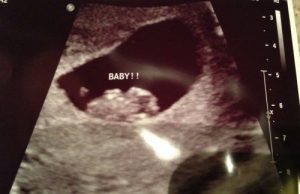

Como é possível ter precisão? Basta prestar atenção na localização da placenta no primeiro ultrassom que a futura mamãe faz durante o período inicial de gestação.

Alguns pais erram ao prever o sexo do bebê porque são guiados pelo lugar que o pequeno ocupa. Não se deve se concentrar na localização do bebê, mas onde a placenta se formará. No início os bebês ficam perto da placenta, mas o mais importante é procurar a área onde a placenta vai se desenvolver.

Se você achar difícil interpretar o ultrassom ou encontrar a placenta, não fique na dúvida. Peça ao seu médico para lhe explique onde a placenta se encontra . Porém, a verdade absoluta em relação ao sexo do bebê só aparecerá após 20 semanas.